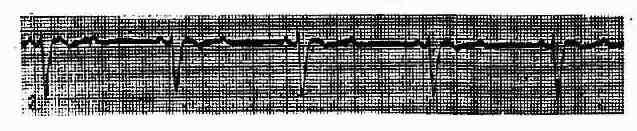

(三)完全性房室传导阻滞 ①P波与QRS波群相互无关;②心房速率比心室速率快,心房心律可能为窦性或起源于异位;③心室心律由交界区或心室自主起搏点维持。

QRS波群的形态主要取决于阻滞的部位,如阻滞位于希氏束分支以上,则逸搏起搏点多源于房室交界区紧靠分支处出现高位心室自主心律,QRS波群不增宽。(图3-3-22)如阻滞位于双束支,则逸搏心律为低位心室自主心律,QRS波群增宽或畸形(图3-3-23)。邻近房室交界区高位逸搏心律的速率常在每分钟40-60次间,而低位心室自主心律的速率多在每分钟30-50次间。

图3-3-22 第三度房室传导阻滞(心室起搏点在房室束分叉以上)

图3-3-23 第三度房室传导阻滞(心室起搏点在房室束分叉以下)QRS波>0.12秒